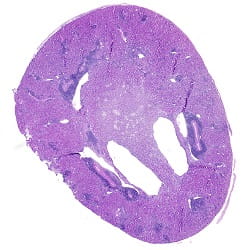

CREDIT: Martin Oberbarnscheidt

CAPTION: Transplanted kidney stained with a blue dye shows signs of inflammation.